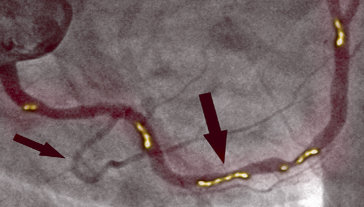

Na obrázku vlevo vidíme zúžení pravé koronární tepny u 66letého muže, diagnostikované pomocí invazivní koronární angiografie. Je vidět významné zúžení v proximální části způsobené zkalcifikovanou aterosklerotickou plakou, která blokuje průtok krve.

Na fotografii vpravo vidíme čistou pravou koronární tepnu, již bez stop zkalcifikované aterosklerotické plaky u stejného pacienta po jednom měsíci terapie. Nejsou zde žádné smrtící cholesterolové usazeniny. Krev proudí volně a zásobuje kyslíkem všechny orgány.